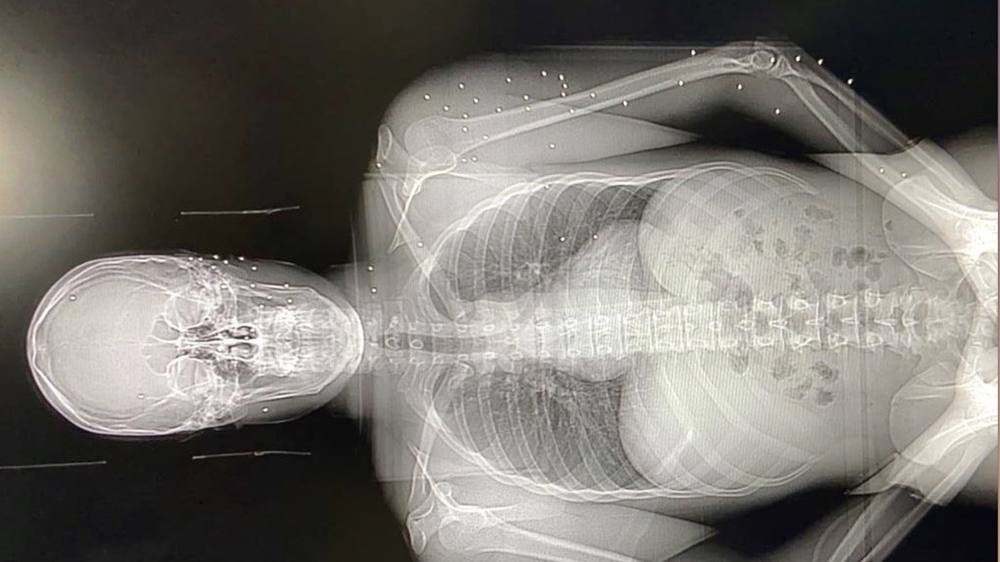

At least 728 people were injured during Saturday’s protest, including many receiving wounds to head, neck and chest. Wounds were consistent with both rubber bullets and birdshot.

One patient was brought in with at least 50 pellets spread across his body.

Chakhtoura said his colleague Dr Elie Saliba had been shot in the head at Saturday’s protests after working long shifts to save victims of the Beirut explosion.